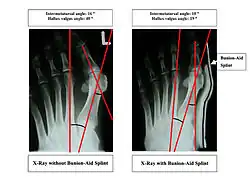

Bunions can be diagnosed and analyzed with a simple x-ray, which should be taken with the weight on the foot.[10] The hallux valgus angle (HVA) is the angle between the long axes of the proximal phalanx and the first metatarsal bone of the big toe. It is considered abnormal if greater than 15–18°.[11] The following HV angles can also be used to grade the severity of hallux valgus:[12]

The intermetatarsal angle (IMA) is the angle between the longitudinal axes of the first and second metatarsal bones, and is normally less than 9°.[11] The IM angle can also grade the severity of hallux valgus as:[12]

Orthotics are splints or regulators while conservative measures include various footwear like toe spacers, valgus splints, and bunion shields. Toe spacers seem to be effective in reducing pain, but there is no evidence that any of these techniques reduces the physical deformity. There are a variety of available orthotics including off-the-shelf commercial products and custom-molded orthotics, which may be prescribed medical devices.[14]